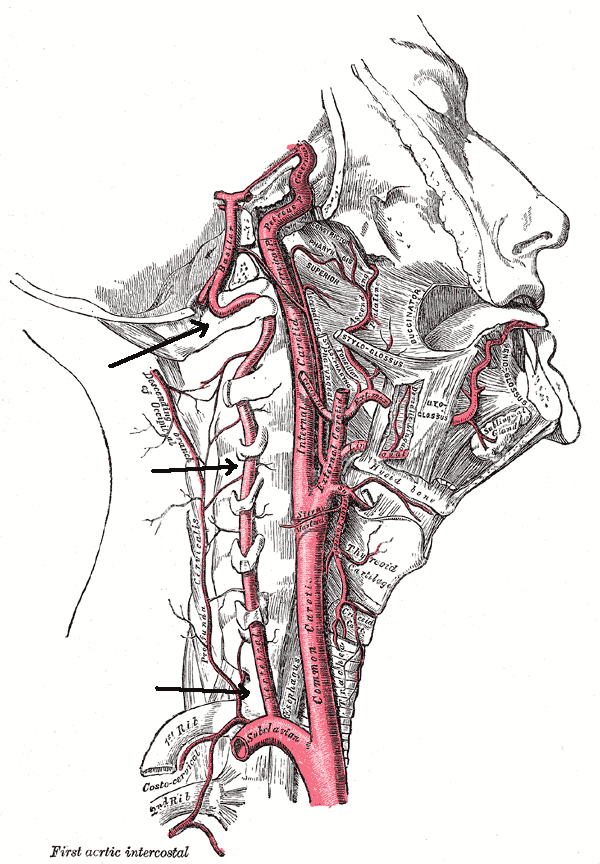

The vertebral arteries usually arise from the first portion of the subclavian artery. They traverse upward between the vertebral bodies and join to form the basilar artery.

The vertebral arteries supply blood to the pons, the medulla and the cerebellum. The basilar artery continues to supply blood to the circle of Willis but also to the midbrain. The vertebral arteries are anatomically divided into 3 extra-cranial and one intra-cranial portions. It is not uncommon for a person to have only one dominant vertebral artery. If the other one is healthy this has little consequence. However, if the healthy vertebral artery develops stenosis or lack of blood flow because of subclavian or aortic disease, then symptoms may arise.